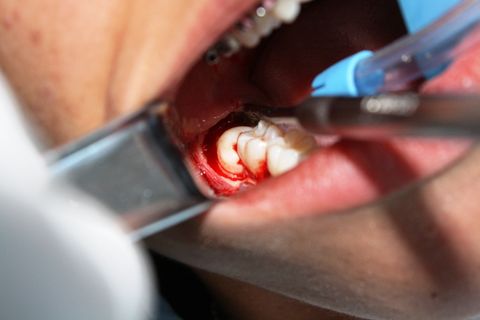

Exodontia 18 e 48

Caso clínico, 01 de Ago de 2014

Paciente AB, sexo feminino, 19 anos, com indicação para exodontia dos elementos 18 e 48 incluso e mesio-incliniado.

Fotos do caso